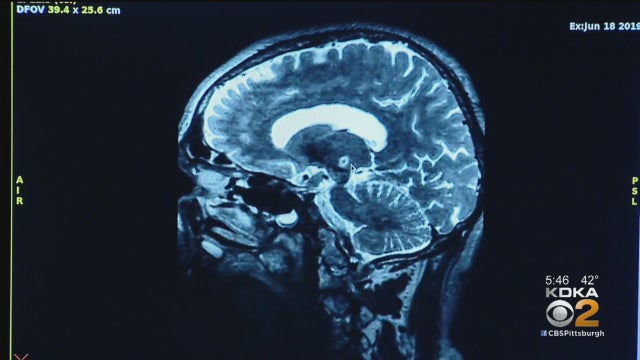

Study: Marathon Training Can Slow The Aging Process

Researchers say if you want to slow the aging process, run a marathon.